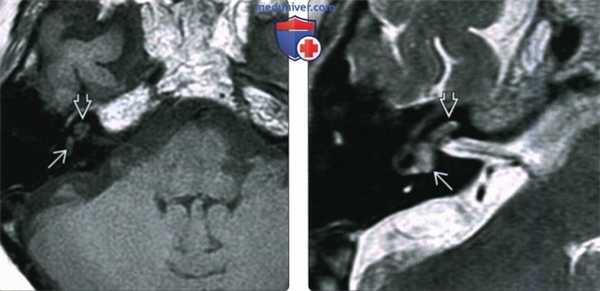

Опухоль эндолимфатического мешка: А. Аксиальная КТ; Б. и В. Аксиальные МРТ до и после контрастирования.

Задняя часть левой пирамиды эрозирована в области эндолимфатического мешка.

Б. опухолевый массив имеет гетерогенную структуру до контрастирования. В. Плотная часть опухоли усиливается при контрастировании.